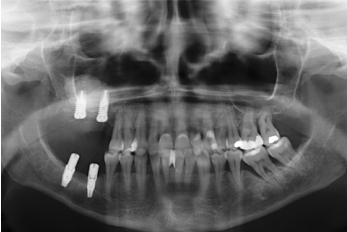

Presentamos el caso de una paciente femenina de 58 años que acude a la consulta dental para valoración de los molares 16 y 17 por dolor y movilidad. En la exploración clínica se observa movilidad de ambos y supuración a nivel del surco. La radiografía confirma nuestro diagnóstico encontrándonos con una pérdida ósea considerable y una perforación sinusal a nivel del ápice de ambos molares (Figura 2).

Finalmente, podemos observar la estabilidad de ambos tratamientos en la radiografía final a los 8 años, donde ambos se mantienen estables sin pérdidas óseas (Figura 13)